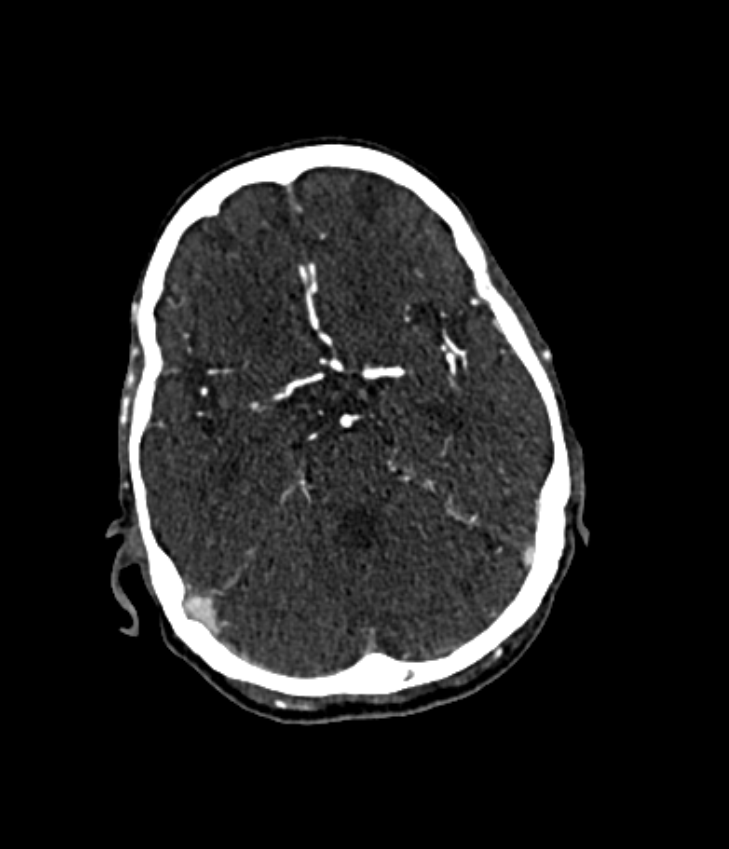

The pipeline we propose receives a CTA image as input, an example of which is shown in Fig. 2(a). Alongside the CTA data, a brain atlas (shown already registered to an example in Fig. 2(c), a mean brain over a patient populations) (Kemmling et al., 2012) together with the corresponding vessel atlas (Forkert et al., 2012) (accordingly transformed, shown in Fig. 2(d)) is given. The latter atlas is a volume representing the existence of voxels belonging to a vessel by means of a probability value, whereby it emphasizes on the arterial branches close to the Circle of Willis. In a first step, all bone structures are removed, as indicated in Fig. 2(a), using a method by Chen et al. (2020) which segments those bone structures in CTA scans. An example is shown in Fig. 2(b) which is the bone segmentation of the slice shown in Fig. 2(a). The CTA volume is not only forwarded to the bone removal but also used to register the brain atlas onto in Fig. 2(b). The non-rigid (elastic) registration is based on Chefd’Hotel et al. (2002)’s method specifically designed to register multi-modal volumes. The resulting deformation field is used to transform the vessel atlas (Forkert et al., 2012) in step Fig. 2(c) into the CTA coordinate system. Tubular structures of the bone-free CTA scan, resulting from Fig. 2(a), are enhanced using the Frangi filter (Frangi et al., 1998) (two scales, σ1=1.00subscript𝜎11.00\sigma_{1}=1.00, σu=1.50subscript𝜎𝑢1.50\sigma_{u}=1.50) exemplarily shown in Fig. 2(e). The filter response is masked in Fig. 2(e) with the vessel atlas, which is binarized with a relative threshold of t1=0.5%subscript𝑡1percent0.5t_{1}=0.5\% (of the maximum value) followed by dilation (with a kernel size in z,y and x of 11, 7 and 7, respectively). Fig. 2(f) shows the result of the vessel masked Frangi response, which is thresholded with t2=4subscript𝑡24t_{2}=4. Values below that threshold are suppressed to zero, values above are kept with the original values. With this step, noise is being reduced which stabilizes the subsequent steps, like the slice-wise circle based Hough transformation in step Fig. 2(f)(canny threshold = 10, accumulator threshold = 1, min distance = 5, min radius = 0, max radius = 5 and accumulator threshold = 1). The goal of the Hough transformation is to identify circle-shaped structures in the given slices, however, as shown in Fig. 2(g) many centerpoints of the detected circles do not match with the preliminary vessel tree segmentation. Hence in the next step, the mask used for the Hough transform is reused again, to mask out in step Fig. 2(g) all centerpoints which do not align with the segmentation. The example shown in Fig. 2(g) originally has 6747 centerpoints in total, reduced to 1375 by the masking, the result of which is shown in Fig. 2(h). The remaining points are used as seed points for region growing in Fig. 2(h). The region growing segments all voxels connected to the seed points, whose intensity differs no more than ±5%plus-or-minuspercent5\pm 5\% from the average intensity of the seed point voxel values. The result is a preliminary segmentation which only includes vessel segments represented in the original vessel atlas. As will be described below, this mask is used for labeling. The result is shown in Fig. 2(i). In order to segment all vessels, especially more distant vessel structures, the segmentation mask of step Fig. 2(h) is transformed into seed points which are used for the final region growing in Fig. 2(h) segmenting every connected voxel with a value in the range of 130 HU to 1500 HU. Its result is the final segmentation, shown in Fig. 2(j). The whole pipeline has been implemented in MeVisLab 3.4, MeVis Medical Solutions AG, Bremen.

3 Data

In total, 171 CTA scans covering the entire head region, acquired at a single clinical site, were available, distributed over 83 male and 88 female patients with an age of 71±13plus-or-minus711371\pm 13 years ranging from 27 to 96 years. In 15 cases, contrast agent injection was unsuccessful, strong metal artifacts disturbed critical regions, or the registration to the atlas (see Sec. 4.1) failed. Of the remaining 156, 99 patients (57%) were LVO positive and had occlusions in the middle cerebral artery (MCA M1 or proximal M2) or the internal carotid artery (ICA). One patient had a complete occlusion in the Basilar Artery with a consecutive under-perfusion in the left and right posterior cerebral artery (PCAL and PCAR). No subjects had an occlusion in the Anterior Cerebral Artery (ACA). All data was acquired using a Somatom Definiton AS+ (Siemens Healthineers, Forchheim, Germany) and reconstructed with a slice thickness of either 1 mm (15 data sets) or 0.5 mm (141 data sets). Both are considered thin slice reconstructions that ensure an accurate distinction of dense nearby vessel branches.